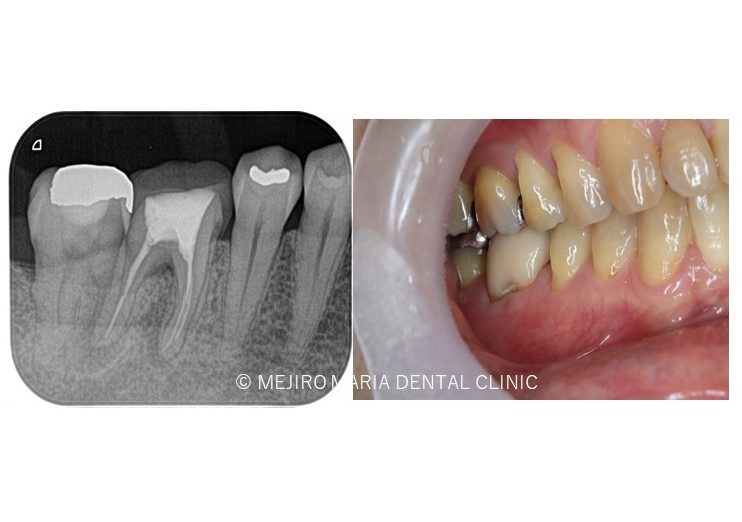

【再根管治療(感染根管治療)】

感染した歯髄や腐敗物、細菌を取り除く治療

再根管治療とは、過去に行った根管治療のやり直しを行う処置です。根尖性歯周炎の原因は根管内に潜む細菌感染ですので、根管内の細菌数を無菌的環境下で減少させ、密に封鎖することで予知性を高めることが可能です。

副作用・リスク

• 根管治療終了後には術後性疼痛がある場合があります

• 根管治療が予後不良の場合は歯根端切除術を行う必要があります